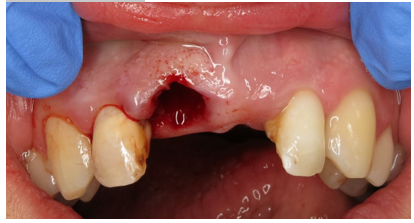

Extraction of the UR1

Single Implant placement UL1 for cantilever bridge

• Immediate implant placement in the UR1 extraction area would be highly risky due to previous infection and skill required to place implant in the correct restorative position